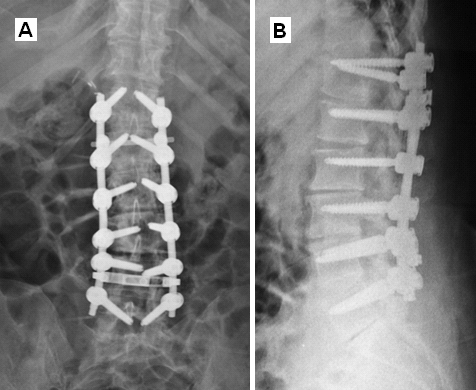

Postoperatif L3-L5 Füzyon Grafisi

Resim 3: Postoperatif direkt grafide L3-L5 seviyelerinde uygulanan pedikül vidası ve rod sistemi ile sağlanan füzyon görülmektedir. L4-L5 mesafesine konulan interbody kafes (cage) omurga diziliminin düzeltilmesine yardımcı olmuştur.